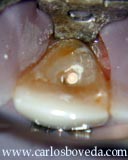

Detalle del abordaje del caso.

Importante remover todo el contenido de este espacio en su correcta longitud y a la vez tener cuidado de no dejar elementos que faciliten la pigmentación de la estructura dentaria.

Detalle de la preparación y de la amplitud del espacio interno de este diente cuando se le compara con una lima K # 140.